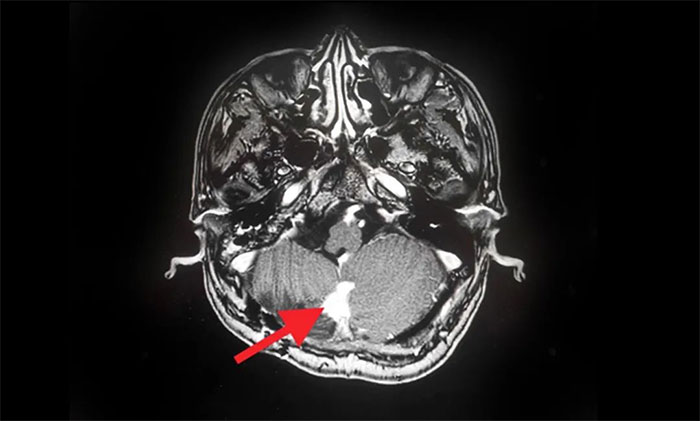

▲ MRI影像复查病灶明显缩小

在伽玛刀治疗后,汪先生身体状况良好,未出现明显并发症,经综合评估顺利出院。8月份,他遵照医嘱来院复查,MRI可见病灶较治疗前明显缩小。

汪先生开心地谈到,经伽玛刀治疗后,头痛症状明显减轻,四肢麻木、行走不稳也得到了改善。目前的他,对回归正常生活充满信心。